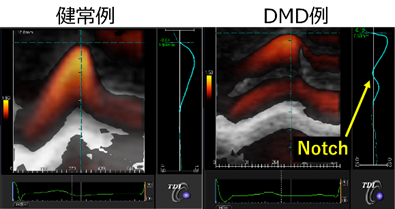

DMDの心筋症を評価する方法は心電図と心臓超音波検査が一般的である。DMDでは心臓超音波検査で心筋症を同定するより早期から、多くの症例で異常Q波やST-T変化などの異常を認めることが知られているが、これらの症例では心電図異常が示唆する心筋梗塞等を発症しておらず、また心電図のQRS電位などの計測値も異常値を示していることが予想されるが詳細な報告はない。心電図検査は多くの施設で簡便に実施できるにもかかわらず心電図異常の意味することは未だに不明のままである。一方で心臓超音波検査においても、通常の心臓超音波検査では正常と判断される症例に対して、微細な収縮低下を検出できるストレイン法の一種であるtransmural myocardial strain profile法を用いると健常者には無いnotchを形成している(Figure4)ことを明らかにしてきたが、左室収縮低下や拡大のメカニズムの解明には至っておらず、依然として不明な事が多い。そこでDMDの心電図や心臓超音波検査結果を用いて、DMDの心筋症の新たな評価方法の確立や、治療薬の評価マーカーとしての知見を見いだす。

Electrocardiography and echocardiography are the most common methods of evaluating cardiomyopathy in DMD. Many patients with DMD show electrocardiography abnormalities such as abnormal Q waves and ST-T changes even before onset of cardiomyopathy diagnosed by echocardiography. However, DMD patients do not present with myocardial infarction as suggested by electrocardiography abnormalities. There are no detailed reports on the relationship between measurements such as QRS amplitude and cardiac function. In other words, despite the fact that electrocardiography testing can be easily performed in many facilities, the meaning of electrocardiography abnormalities remains unclear. In the echocardiography, we have reported that transmural myocardial strain profile, which is a type of strain method that can detect a subtle LV systolic dysfunction, shows an abnormal notch in patients with LV normal contraction by conventional echocardiography (Figure4). However, the mechanism of LV systolic dysfunction and dilation has not yet been clarified, and much remains unknown. Therefore, using the electrocardiography and the echocardiography in DMD, we will establish a new evaluation method for cardiomyopathy in DMD, and develop knowledge for evaluation markers for therapeutic medication.